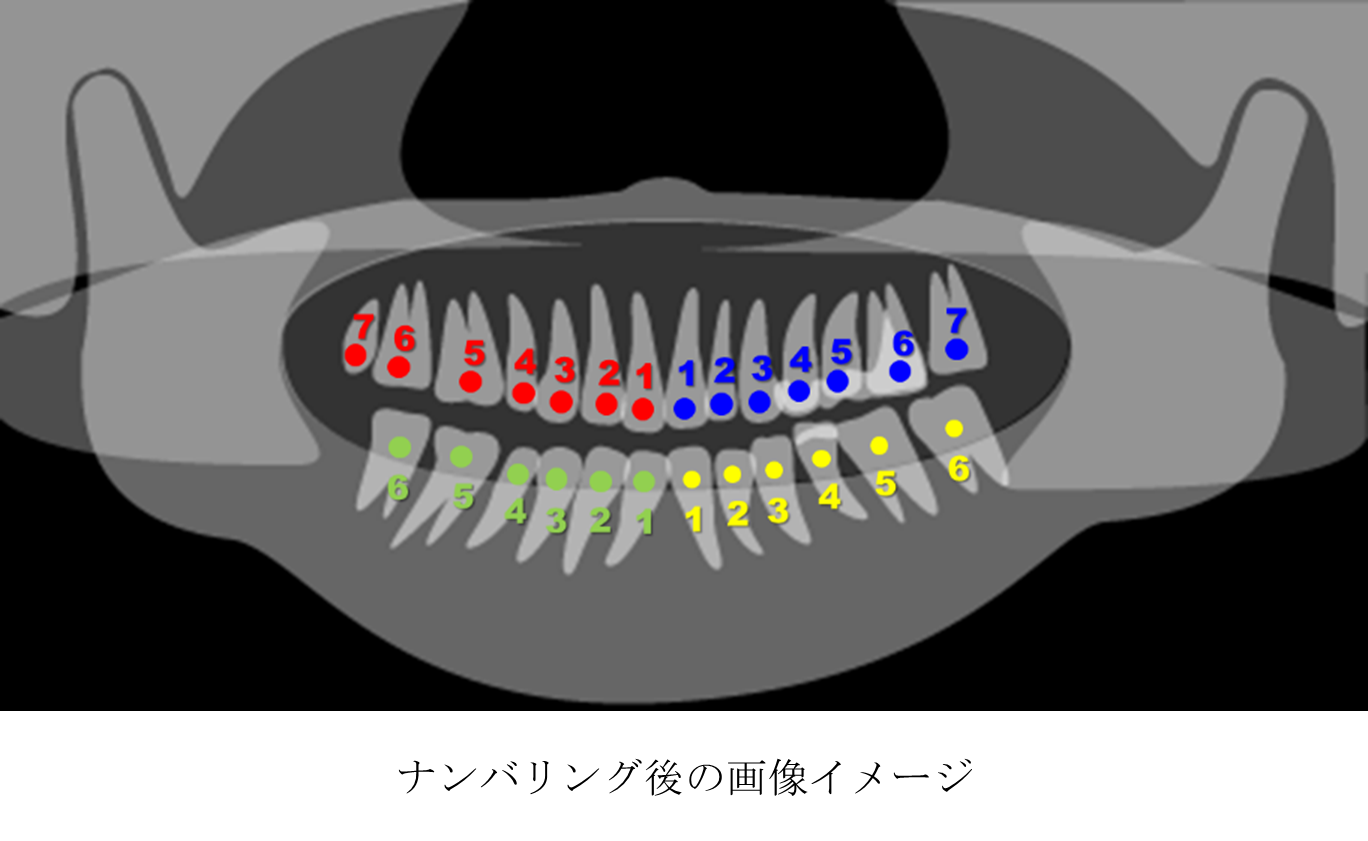

(2)ナンバリング

プログラムを用いて、付与されたマークを画像中央付近からナンバリングします。

前段のナンバリングを行うことで、切り出した歯がどの歯であるかが識別できるようになっています。